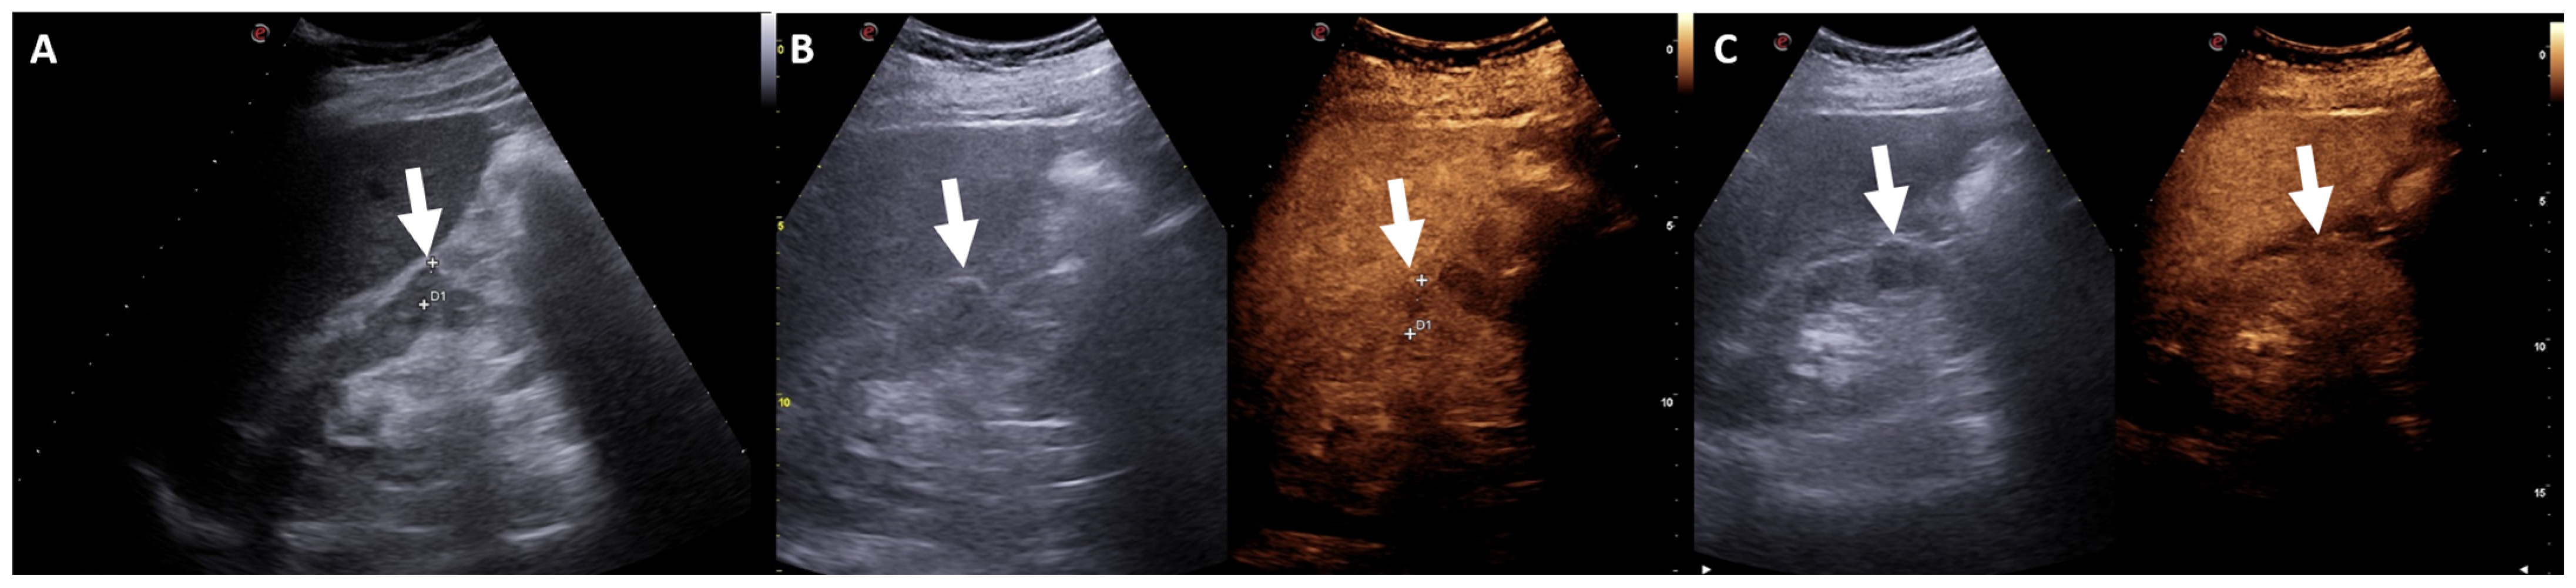

2. Ultrasound Assessment

3. Contrast-Enhanced Ultrasound Assessment